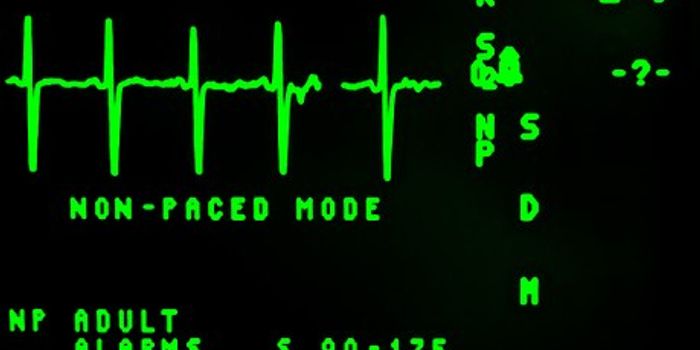

JUN 23, 2017Health & MedicineDo breast implants skew the results from an electrocardiogram (ECG) reading leading to a false diagnosis of a heart atta ...

DEC 10, 2018Health & MedicineIf you or a loved one has been scheduled for a treadmill stress test, you may be wondering what you can expect. The proc ...